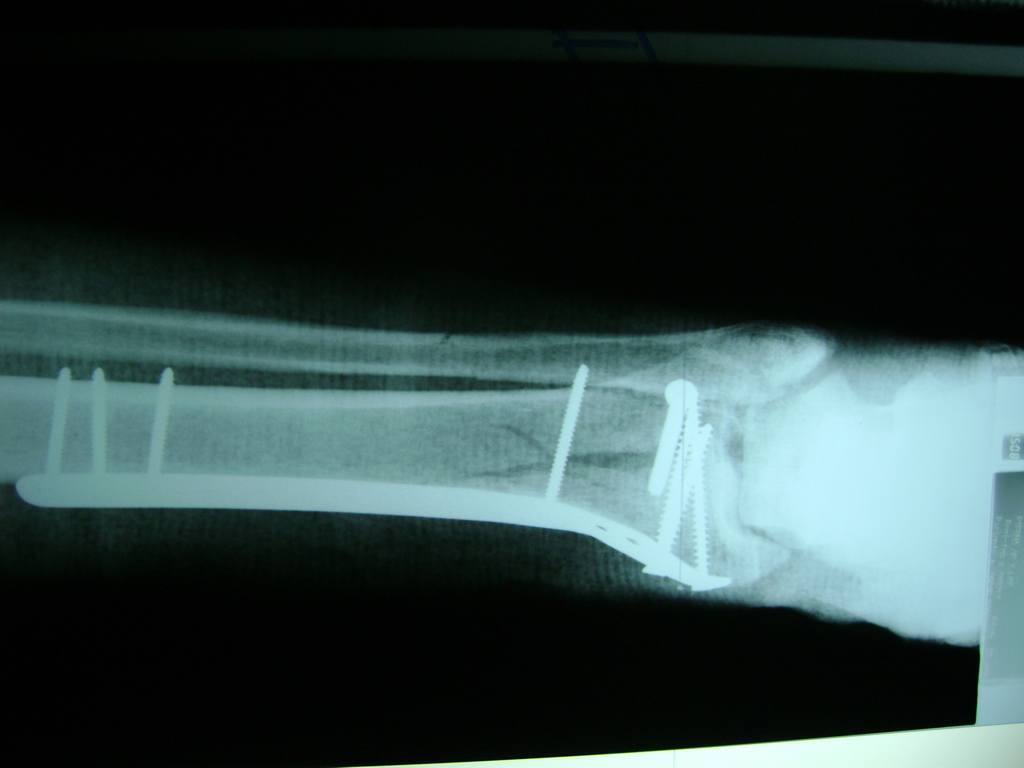

Cirugía de Muñeca y Mano